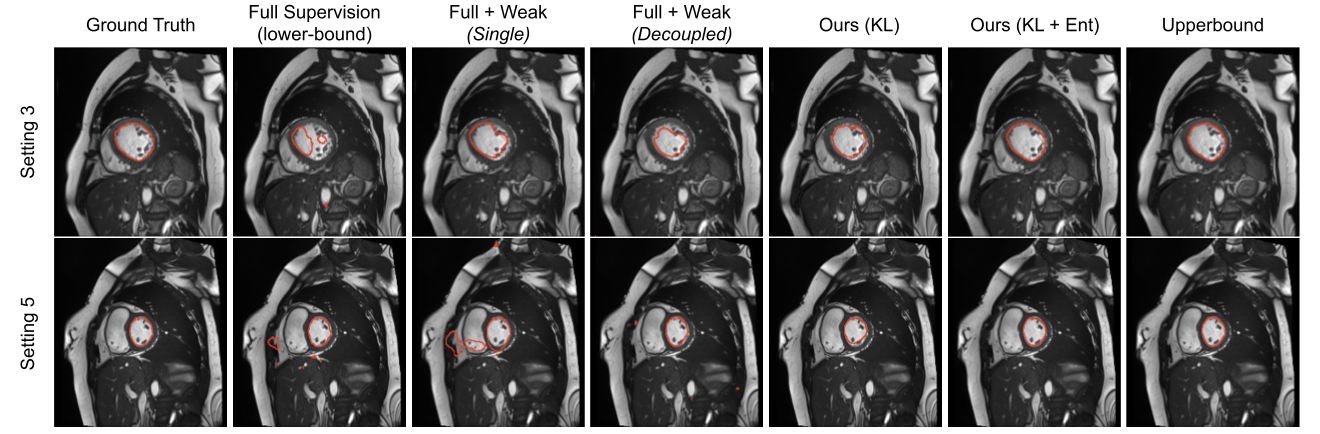

Figure 8: Qualitative results for the analyzed models under two different settings.

In addition to the numerical results presented before, we also depict qualitative results in Fig. 8 and Fig. 9. Particularly, Fig. 8 depicts the segmentation results for the models evaluated in Table 1. We see that results obtained by models with a single network typically under-segment the object of interest (first row) or generate many false positives (second row). Decoupling the decoding branches might reduce the false positive rate, however, it also tends to under-segment the target. Finally, we observe that both of our formulations achieve qualitatively better segmentation results, with the KL+Ent model yielding segmentations similar to those generated by the upper bound model. Furthermore, in Fig. 9, we illustrate additional qualitative results of our models. We observe that without the entropy term our model produces less confident predictions, which results in more noisy segmentations.